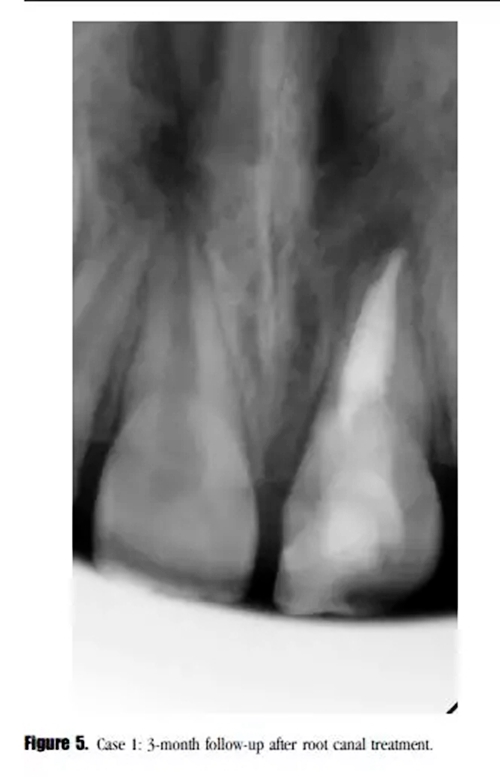

在3個(gè)月后的回訪中,患者癥狀消失,X線顯示根尖透射區(qū)域減小。(圖5)